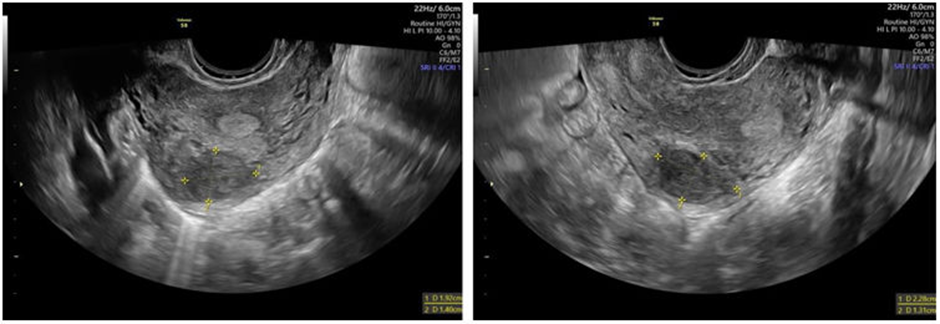

The incidence of leiomyomas during pregnancy is reported to range between 0.1% and 10.7% of all pregnancies. According to a study by De Vivo et al., 71.4% of leiomyomas increased in size during the first and second trimesters, and 66.6% continued to grow between the second and third trimesters. They are more commonly seen in pregnant individuals who are over 35 years old, nulliparous, or of African American descent. While many pregnancies with leiomyomas proceed without issues, the presence of leiomyomas does raise the risk of complications. Rapid leiomyoma growth during pregnancy can lead to significant pain. However, regression of leiomyomas after childbirth has been observed in 72% of women, with a volume reduction of more than 50% between early pregnancy and 3–6 months postpartum. This regression was less common in women who had a miscarriage or used progestins after delivery, whereas mode of delivery (including cesarean), use of other hormonal contraceptives, or breastfeeding did not significantly affect regression. For women with leiomyomas considering pregnancy, evaluation should include a pelvic examination and ultrasound to assess the size and location of the leiomyoma (Figure 1). In patients undergoing assisted reproductive techniques, a saline infusion sonogram before conception is useful for identifying submucosal leiomyomas; alternatively, office hysteroscopy can be performed to evaluate the endometrial cavity. Once pregnant, understanding the leiomyomas' position in relation to the placenta and cervix is important for anticipating potential placental complications.

Figure 1: Transvaginal ultrasound exam [11]